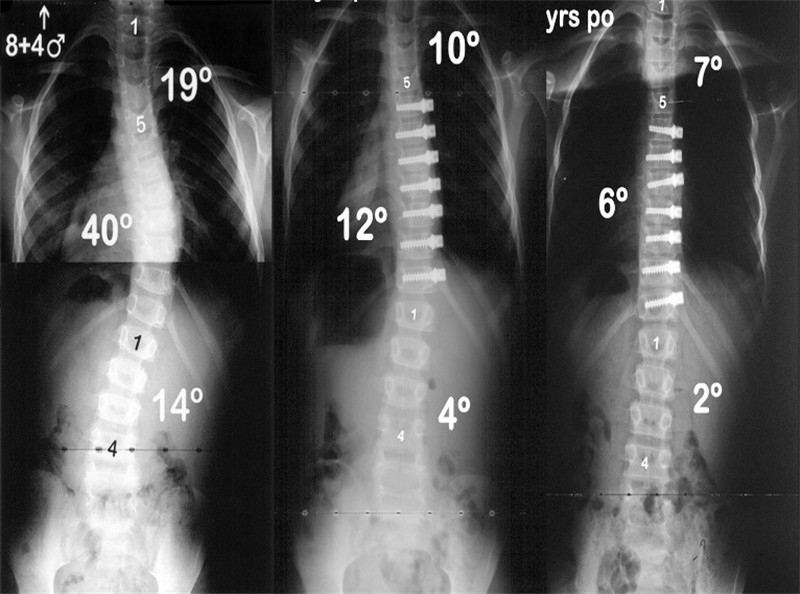

2010年,McCarthy[13]于11例动物模型中应用Shilla技术治疗,结果显示:平均的生长长度为48mm,解剖仅观察到微小的磨损但无断钉断棒等;McCarthy[14]于2014年又报道了38例行Shilla技术治疗的患者,术后3个月予以支具保护,随访2年以上(图 3),术前Cobb角平均为70.5°,术后6周为27°;2年随访示肺容量改善13%,躯干高度(C7-S1)增长12%,出现了3例棒相关并发症,2例感染。